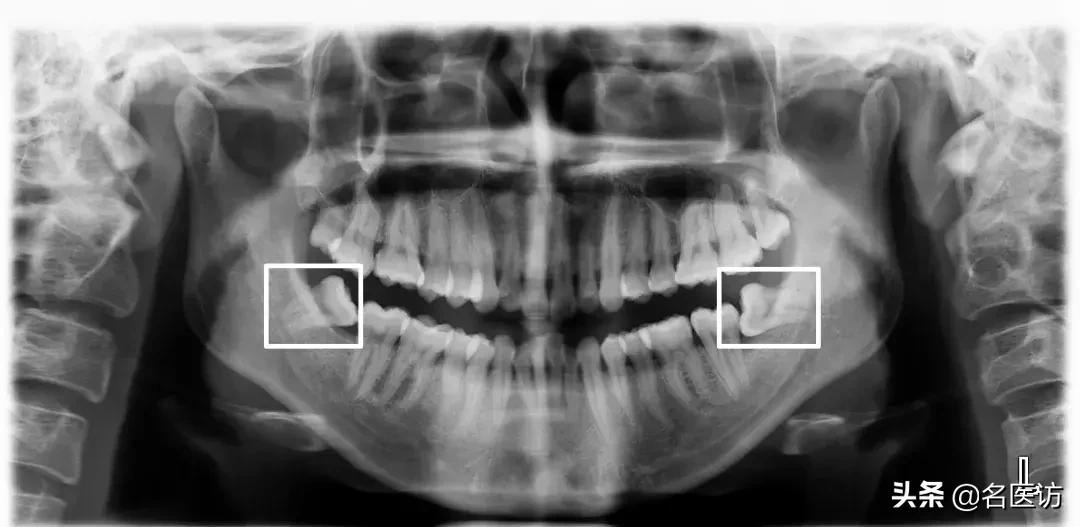

2、牙齿异常

阻生牙、埋伏牙和恒牙的先天缺失是错颌畸形的原因之一。阻生牙常压迫相邻牙齿并导致相邻牙齿牙根的吸收,而阻生的第三磨牙(俗称智齿)如果没有在矫正前拔除,很可能会成为日后牙齿问题复发的罪魁祸首。

埋伏牙

多生牙

阻生牙